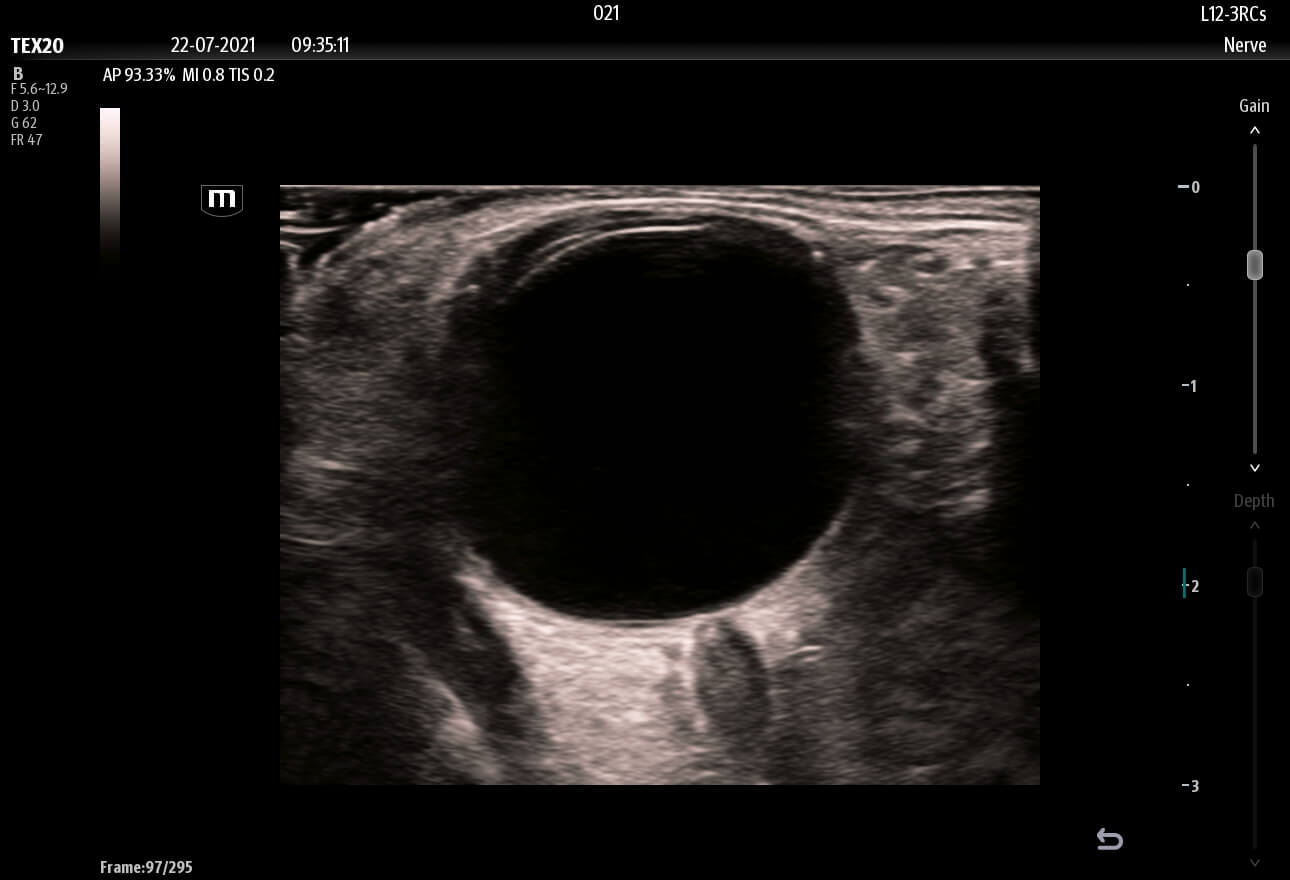

Enhancing Clinical Confidence

Advanced Technologies